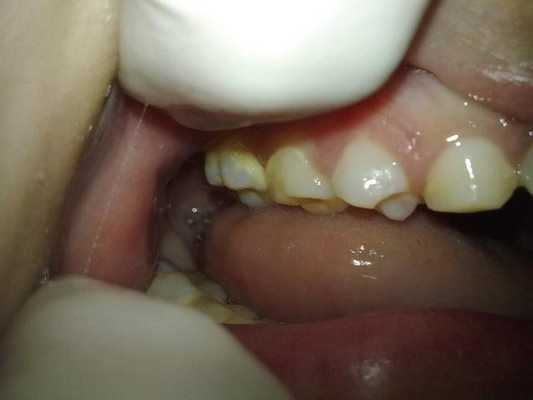

Поверхность зубов была покрыта налетом, а в районе жевательных зубов верхней и нижней челюстей, а также на фронтальных зубах нижней челюсти было диагностировано присутствие наддесневого зубного камня (фото 3).

Фото 3: Внутриротовые проявления: наличие зубного камня.